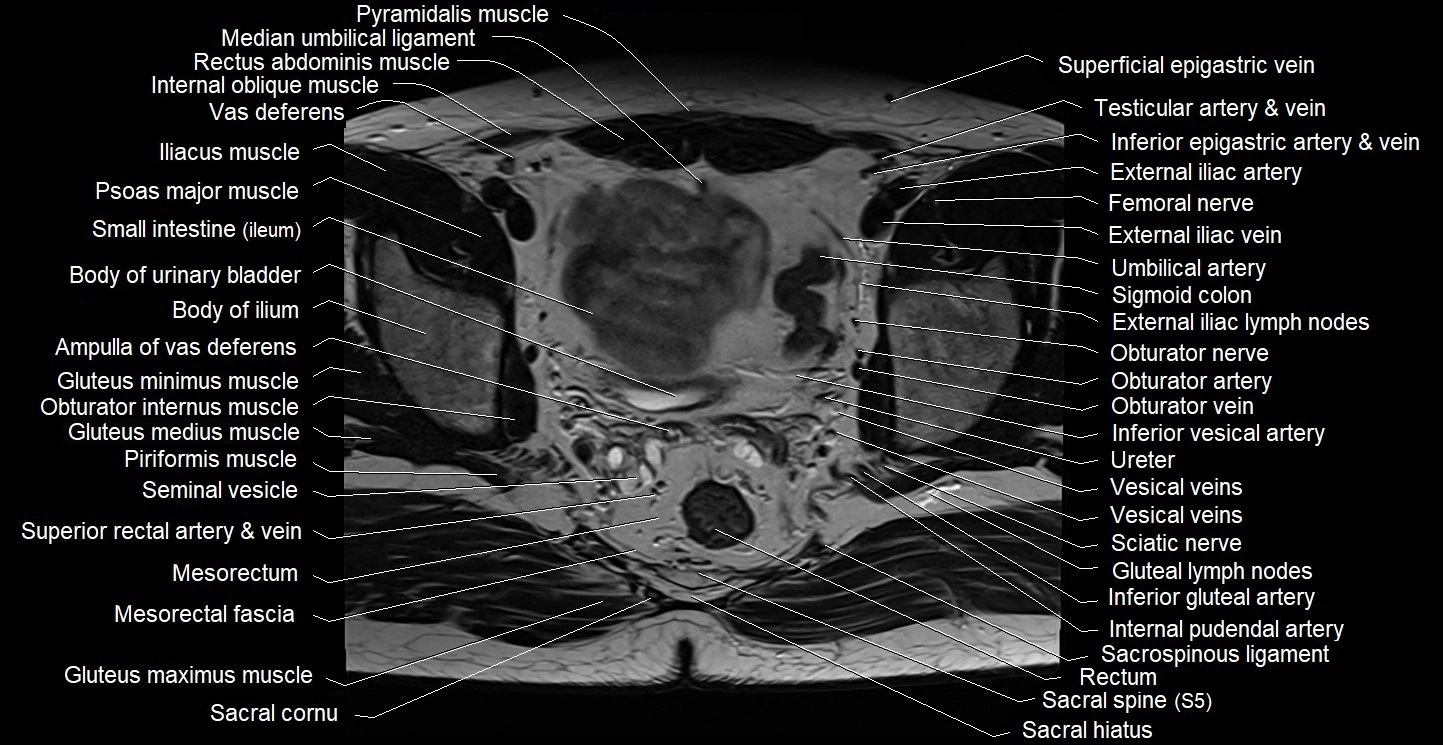

- Ampulla of vas deferens

- Body of ilium

- Body of urinary bladder

- Central zone of prostate

- External iliac artery

- External iliac lymph nodes

- External iliac vein

- Femoral nerve

- Femoral vein

- Genitofemoral nerve

- Gluteal lymph nodes

- Gluteus maximus muscle

- Gluteus medius muscle

- Gluteus minimus muscle

- Inferior gluteal artery

- Inferior vesical artery

- Internal iliac artery

- Internal oblique muscle

- Internal pudendal artery

- Left ureter

- Median umbilical ligament

- Mesorectal fascia

- Mesorectum

- Obturator artery

- Obturator externus muscle

- Obturator internus muscle

- Obturator nerve

- Obturator vein

- Peripheral zone of prostate

- Piriformis muscle

- Psoas major muscle

- Pubic bone

- Pyramidal muscle (pyramidalis muscle)

- Rectum

- S (Sacral spine)

- Sacral canal

- Sacral cornu (sacral horn)

- Sacral hiatus

- Sacral plexus

- Sacrospinous ligament

- Seminal vesicle

- Sigmoid colon

- Superficial inguinal lymph nodes

- Transversus abdominis muscle

- Umbilical artery

- Ureters

- Vas deferens

- Vesical veins